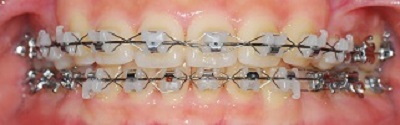

치아 사진 보실게요~

정면 사진

지금까지는 치아의 배열을 맞추는 데 열중 했다면

이제부터는 위아래의 교합을 맞출 거라고 하셨어요

그래서 위 아래 철사를 다시 감았답니다~~~